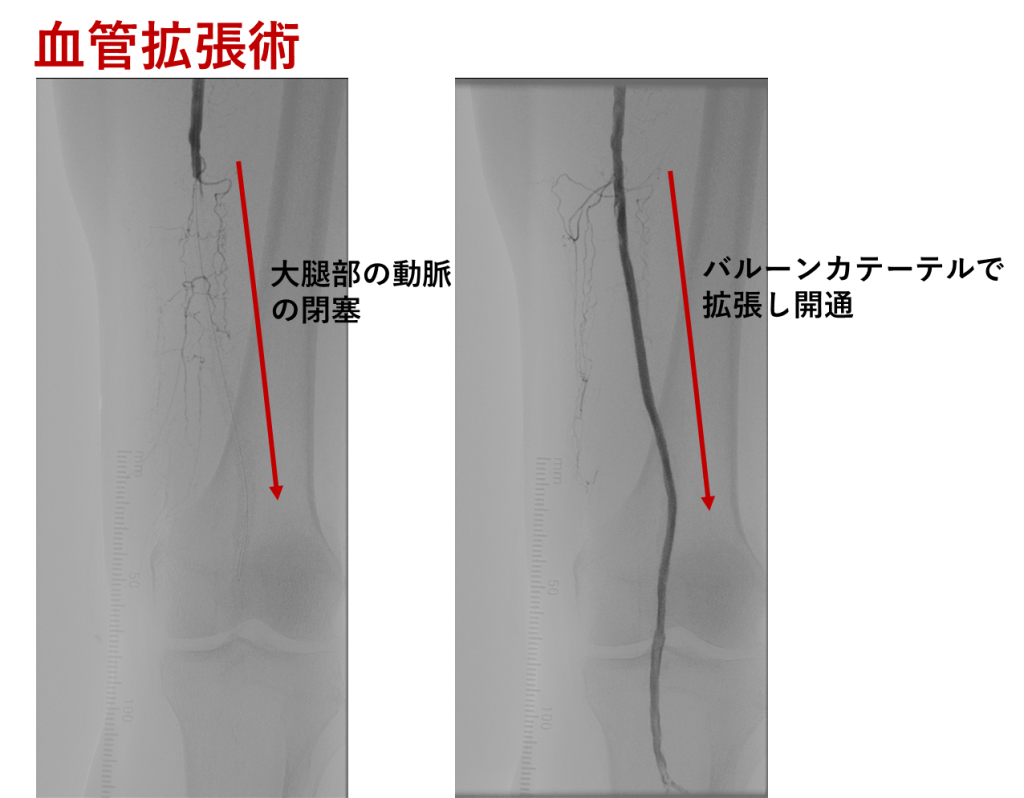

[血管内治療]

カテーテルという細い管を使って動脈の中から治療する方法です。風船やステントで血管を広げて血流を改善する方法です。皮膚を大きく切開する必要がなく、身体への負担が少ないことが特徴です。